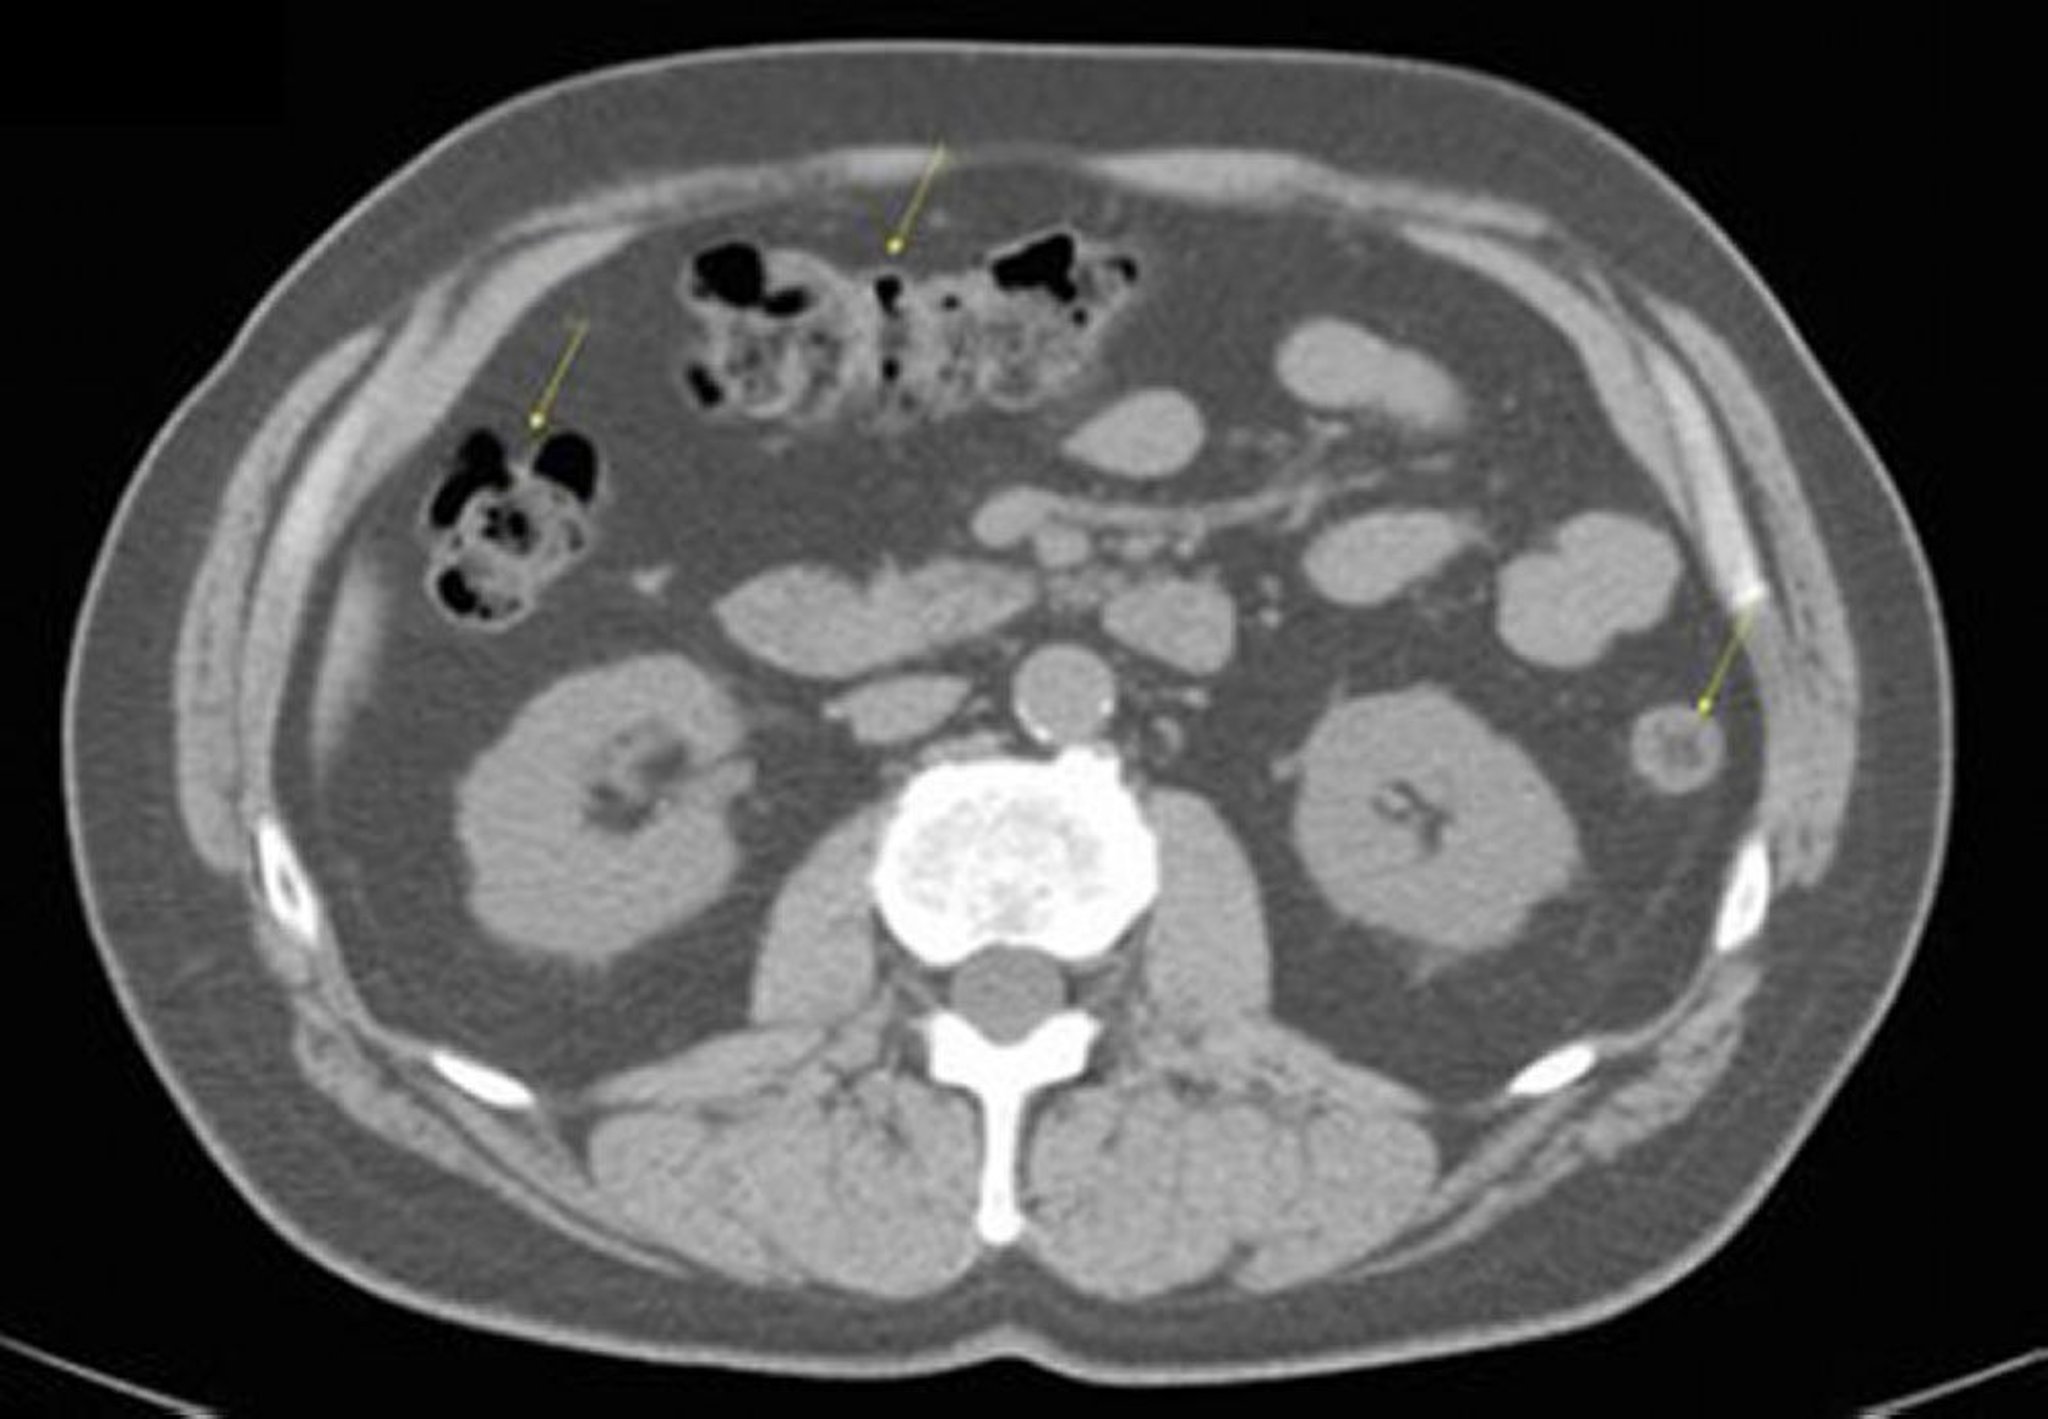

Tomografía computarizada sin contraste de abdomen y pelvis que muestra anatomía normal (corte 17)

Esta imagen muestra el colon (flechas).